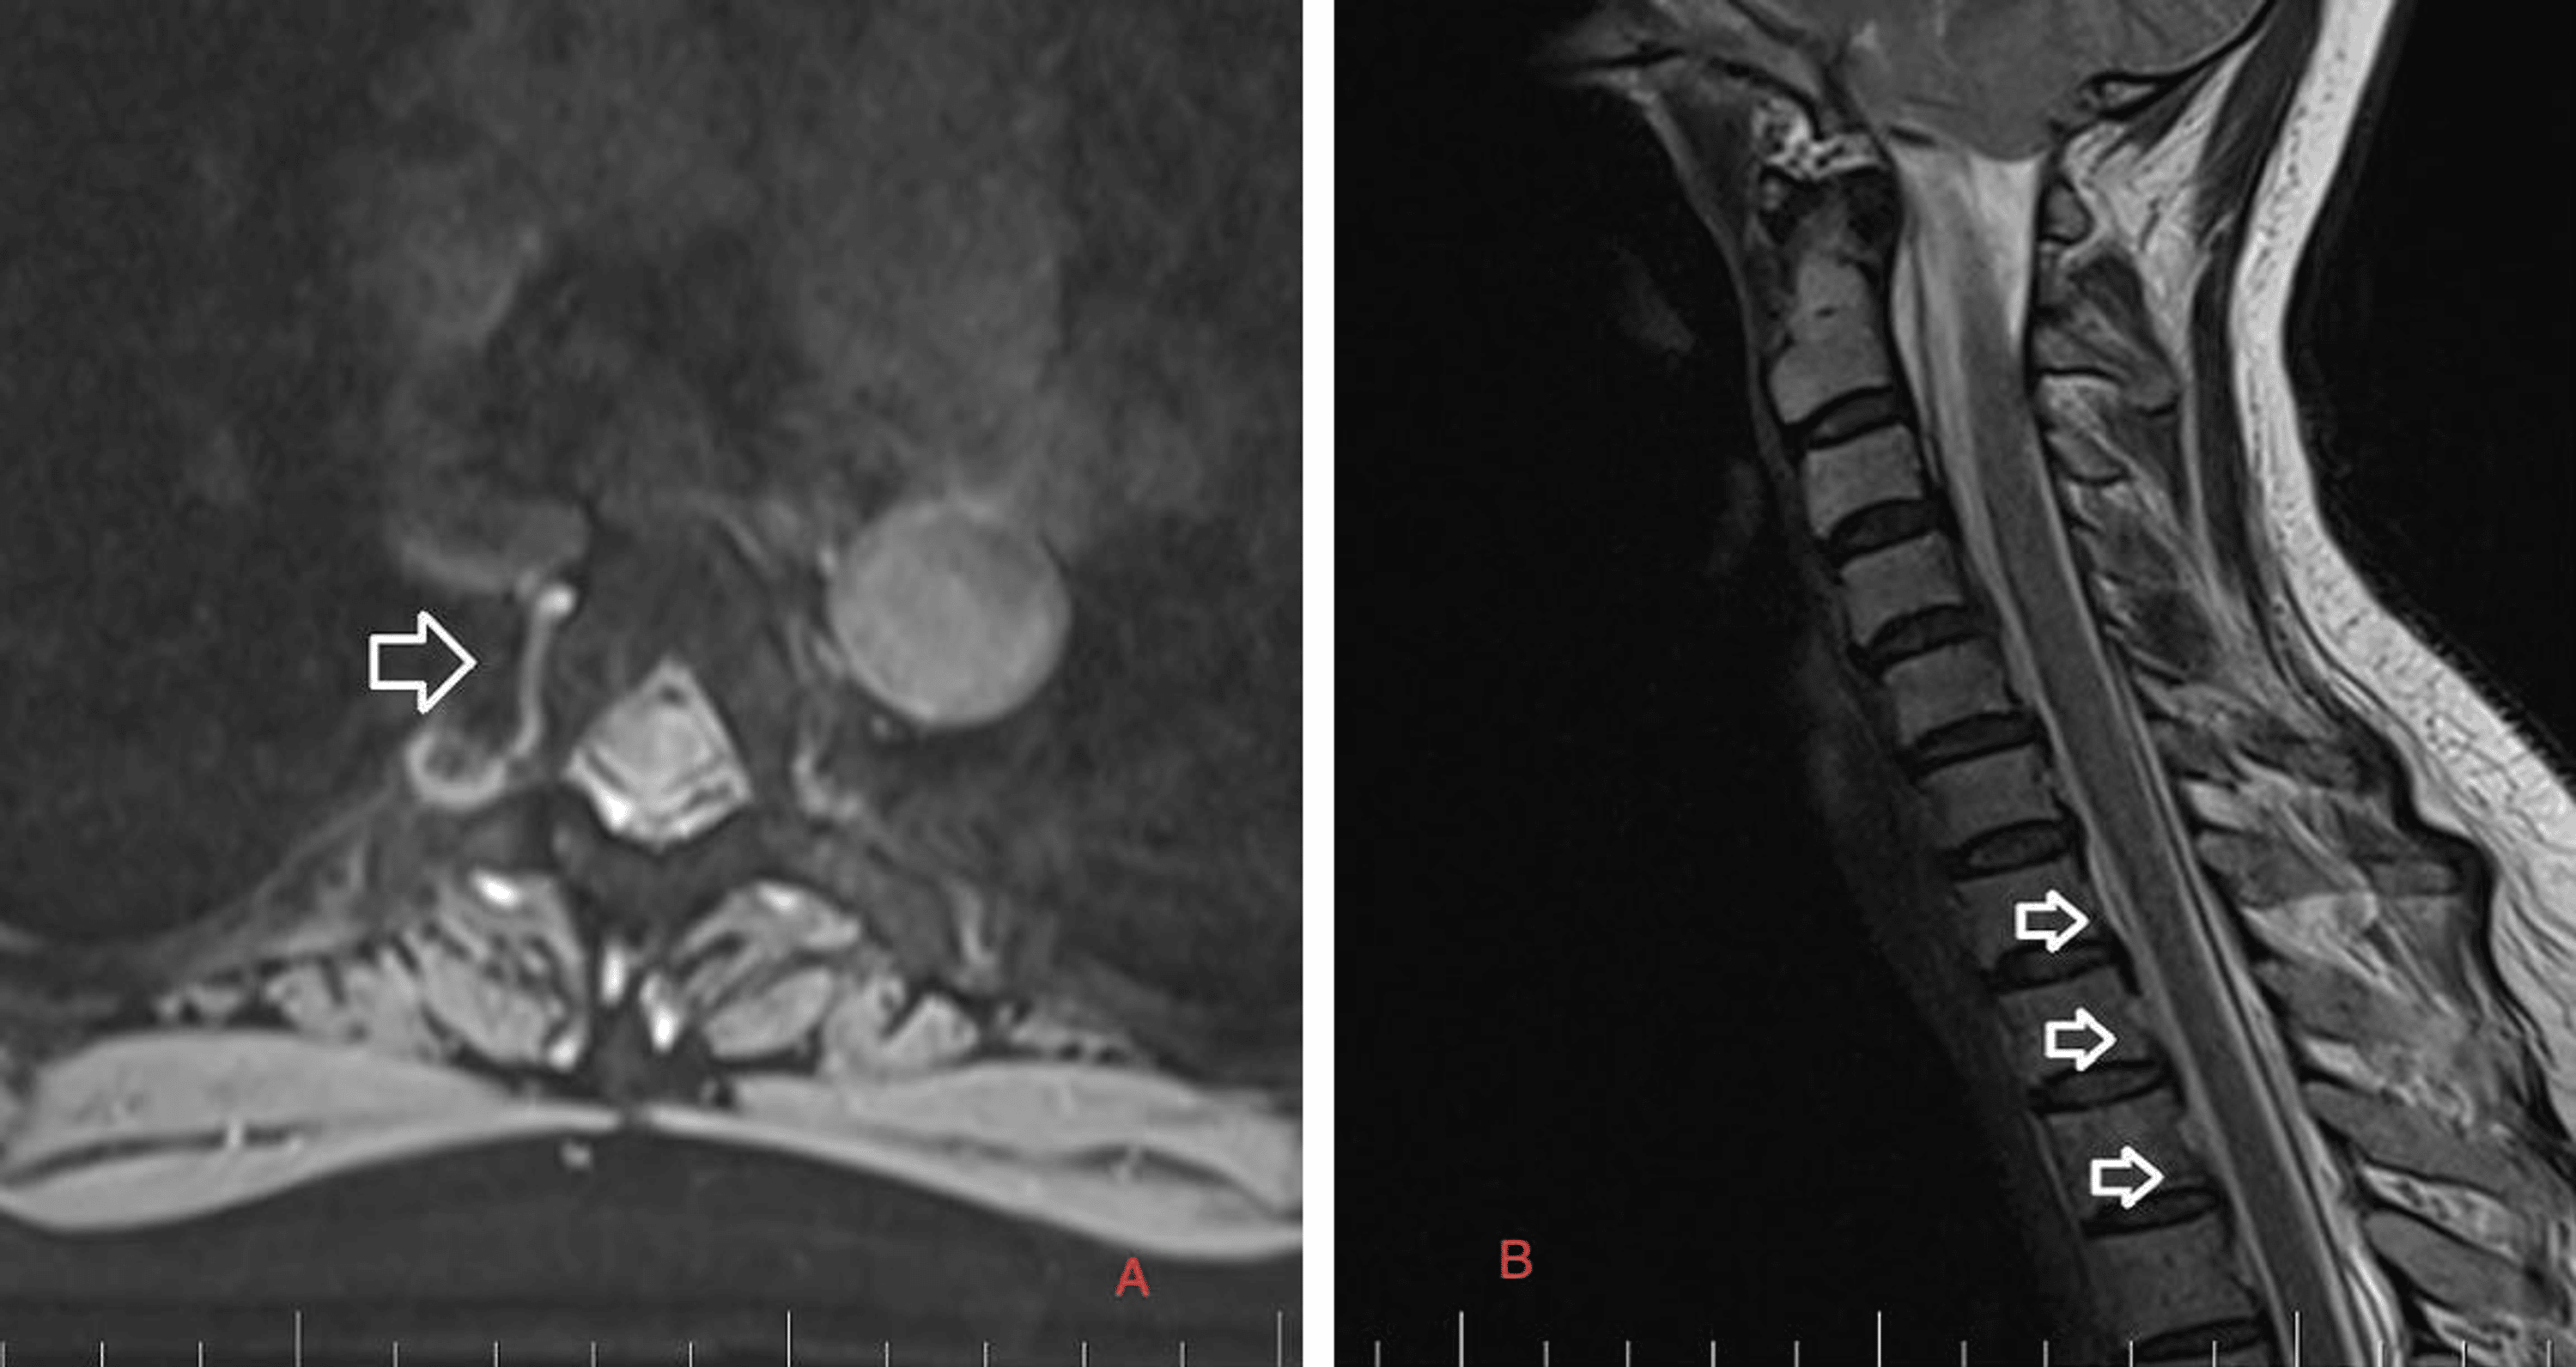

Precisely locating the site of the CSF leakage is fundamental to successful treatment [8]. Hence, on February 2, 2023, we performed a C spine MRI. At the level of C7/T1/T2, a T1 right foraminal CSF leak, as well as the spinal longitudinal extradural fluid collection (SLEC) caudal to the C5 level was detected (Figure 2). This finding confirmed the CSF leak outside the dural sac. It was an SLEC 1b type of CSF leak [4].